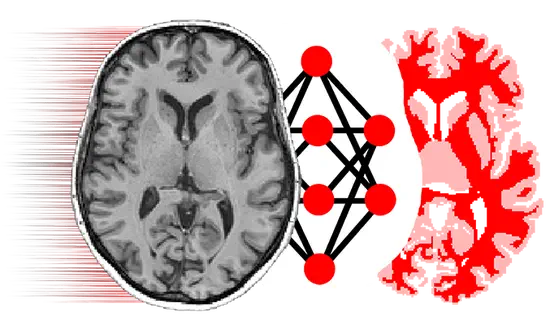

We design learning-based approaches for multi-modal reasoning

Medical imaging is a core source of information in our research

Open source PyTorch implementation of “Dorent, R., Booth, T., Li, W., Sudre, C. H., Kafiabadi, S., Cardoso, J., … & Vercauteren, T. (2020). Learning joint segmentation of tissues and brain lesions from task-specific hetero-modal domain-shifted datasets. Medical Image Analysis, 67, 101862 (📖).”